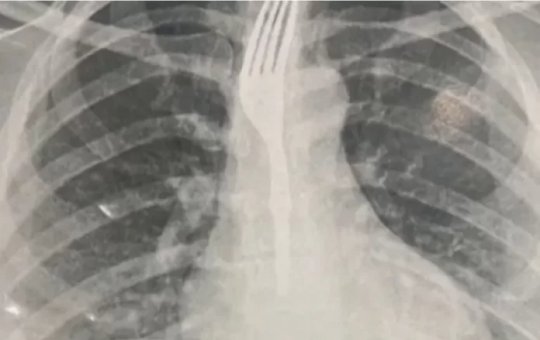

Caso inusitado: mulher engole garfo durante refeição em Guanambi

Paciente foi transferida para Vitória da Conquista; caso é considerado grave